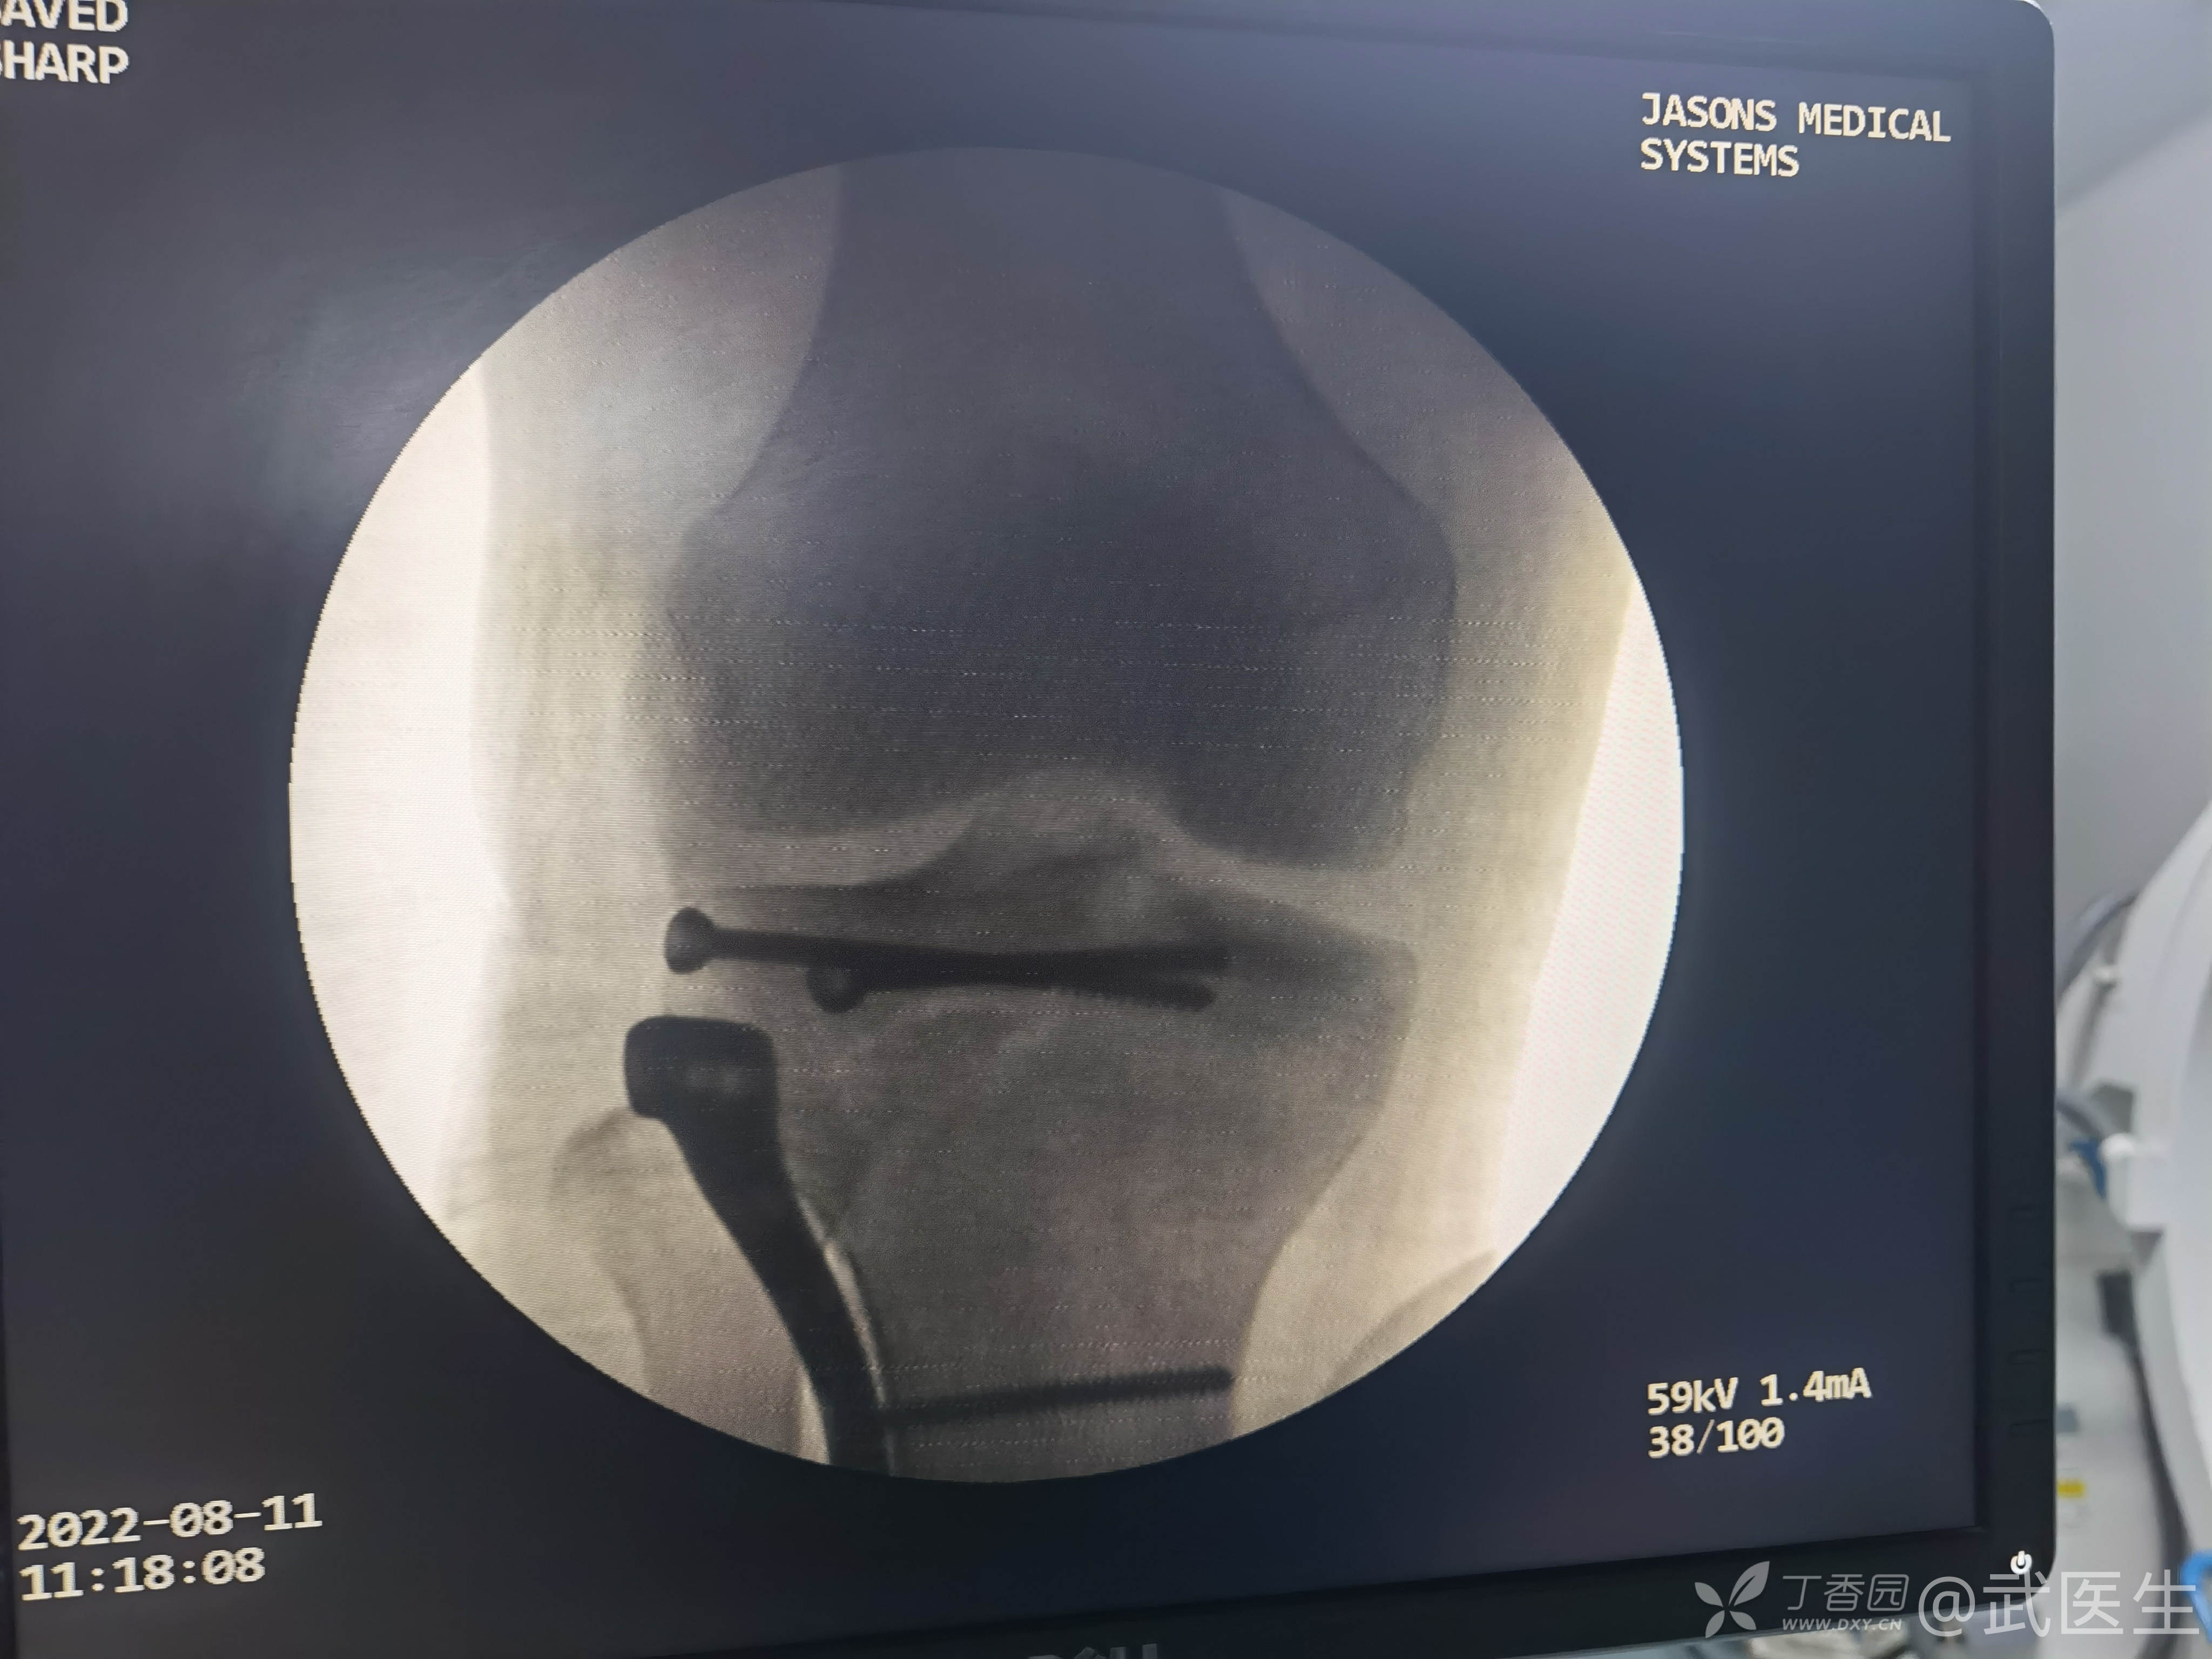

男,15岁,骑摩托车摔伤致右膝疼痛,出血,活动受限三小时就诊,门诊诊断“右胫骨平台骨折,右膝挫裂伤”急诊入院,片子如下,受伤体位照缺失

15岁,骨骺存在,关节加压固定,外侧板支撑